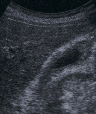

胆嚢腺筋腫症

右肋弓下縦走査